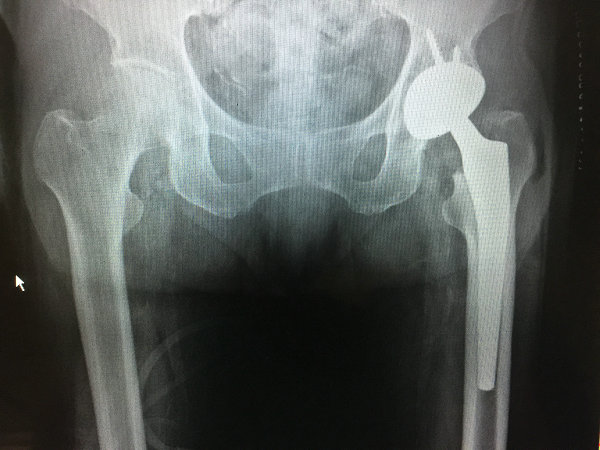

术前

术后

在这种情况下,betway在线登陆关节科经过反复论证以及专家评估,最终决定帮孙老太进行髋关节置换手术。如何解决偏瘫老人术后可能出现的关节脱位问题呢?邱东新手术团队经过多次术前讨论,反复对比,选择了一款比较特殊的关节置换假体,相对来说这一款假体比常规的假体脱位率要低。同时,保证手术中的精准操作,保护好韧带、肌肉,维持好肌肉适度的张力,术后再进行详细的康复指导,确保手术的良好疗效。